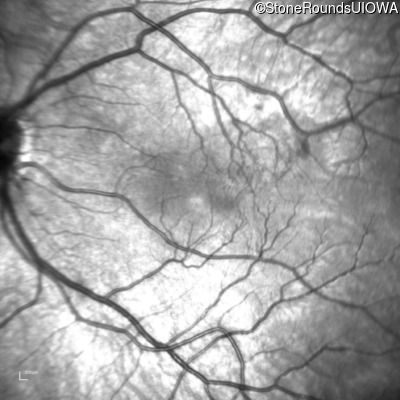

Infrared Fundus Photograph - Right - 20/2000

Exemplar